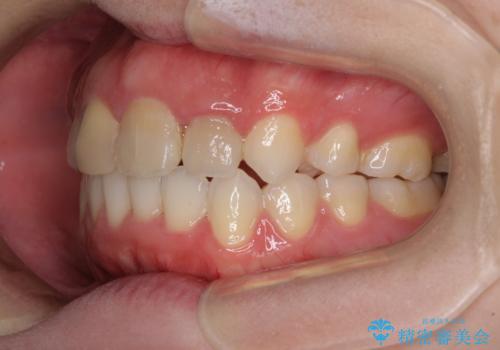

抜歯矯正の後戻り インビザラインによるオープンバイトの再矯正

- 以前矯正治療をされていましたが、後戻りが起きたことを気にして来院された患者様です。

上下前歯のオープンバイトを改善するため、インビザラインにて治療を行うこととしました。